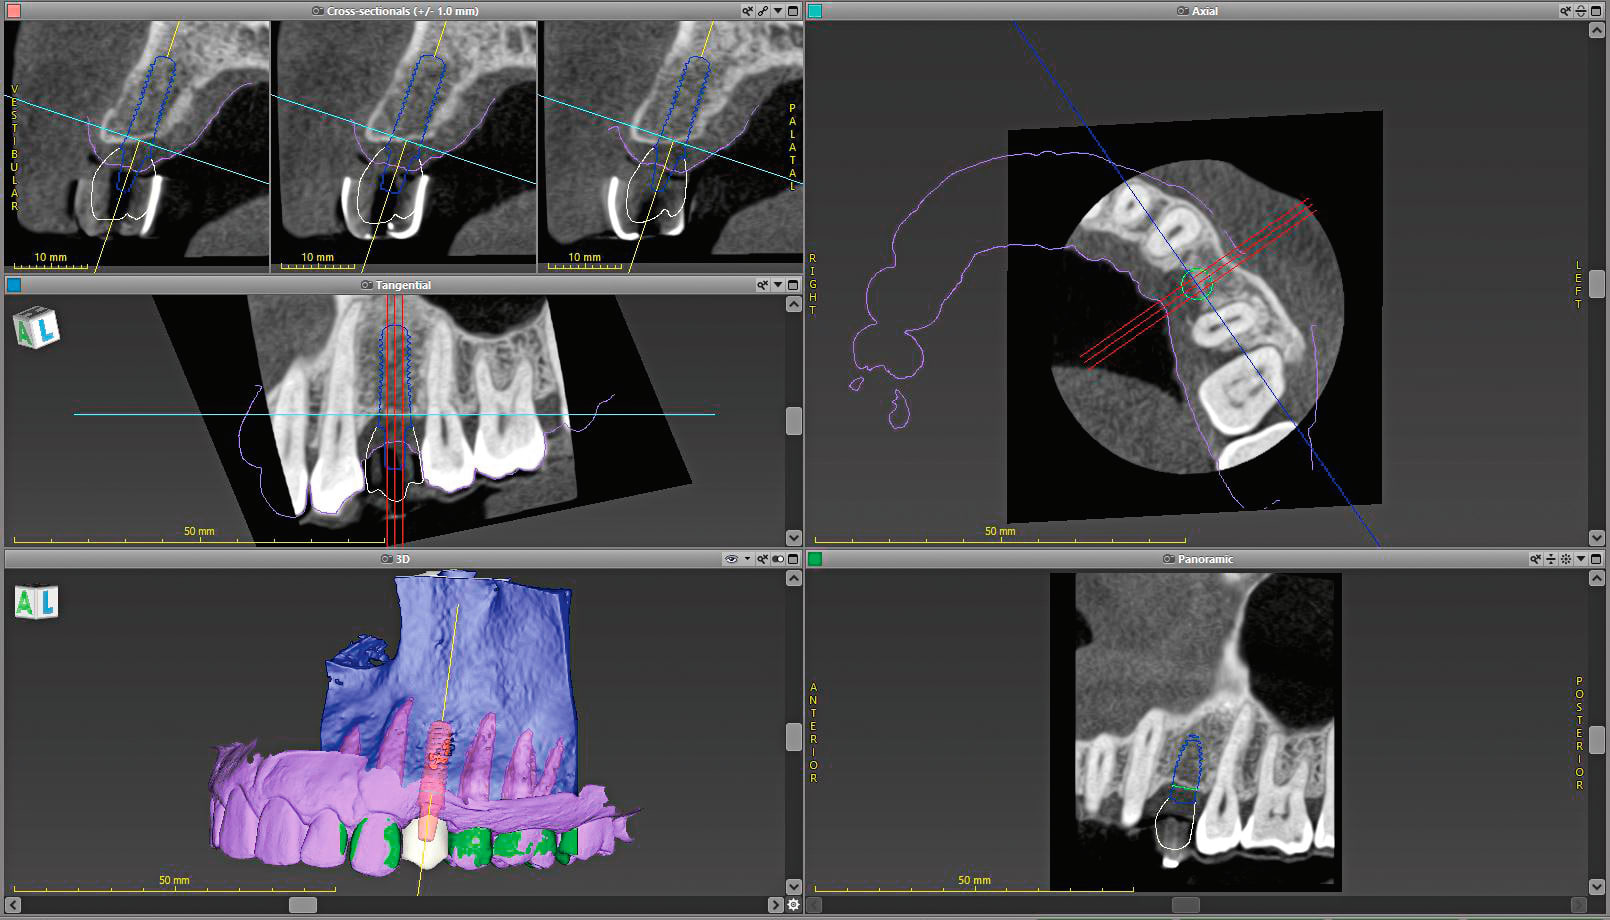

The patient was sent to have a cone-beam computed tomography (Morita, www.morita.com) taken of the area in question. Digital diagnostic impressions were also taken using an intraoral scanner (Trios® 3, 3Shape, www.3shape.com). Once these were obtained, the digital imaging and communications in medicine (DICOM) files were imported into the implant planning software (coDiagnostiX®, Dental Wings, www.dentalwings.com), while the scan files were imported into the laboratory software (Straumann® CARES® Visual, Straumann) (Figure 1 and Figure 2). Because the Straumann PURE Ceramic Implant is monobody in design and it is not recommended to modify the abutment,3 the DWOS Synergy™ workflow (Dental Wings) was utilized to virtually plan this case.

DWOS Synergy provides real-time communication between the implant planning software (coDiagnostiX) and the laboratory software (Straumann CARES Visual). This feature improves implant planning by allowing the visualization of the relationship between the proposed implant position and the proposed restoration. Modifications made to the implant position or restoration design are immediately transferred to the other software, providing instantaneous feedback on how the modification of one affects the other. Of particular interest regarding the Straumann PURE Ceramic Implant is that one can design the restoration and be assured that the planned position will not require modification for restorative materials.